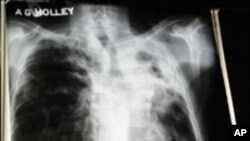

جنوبی افریقہ : تپ دق کی ویکسین پر تجربات جاری

حال ہی میں جنوبی افریقہ میں تپ دق کے مرض پر مؤثر کنٹرول کے لیے ایک نئی ویکسین کی تیاری کے منصوبے کا اعلان کیا گیا ہے، جس سے اس موذی مرض سے بچاؤ میں مدد ملنے کا امکان ہے۔